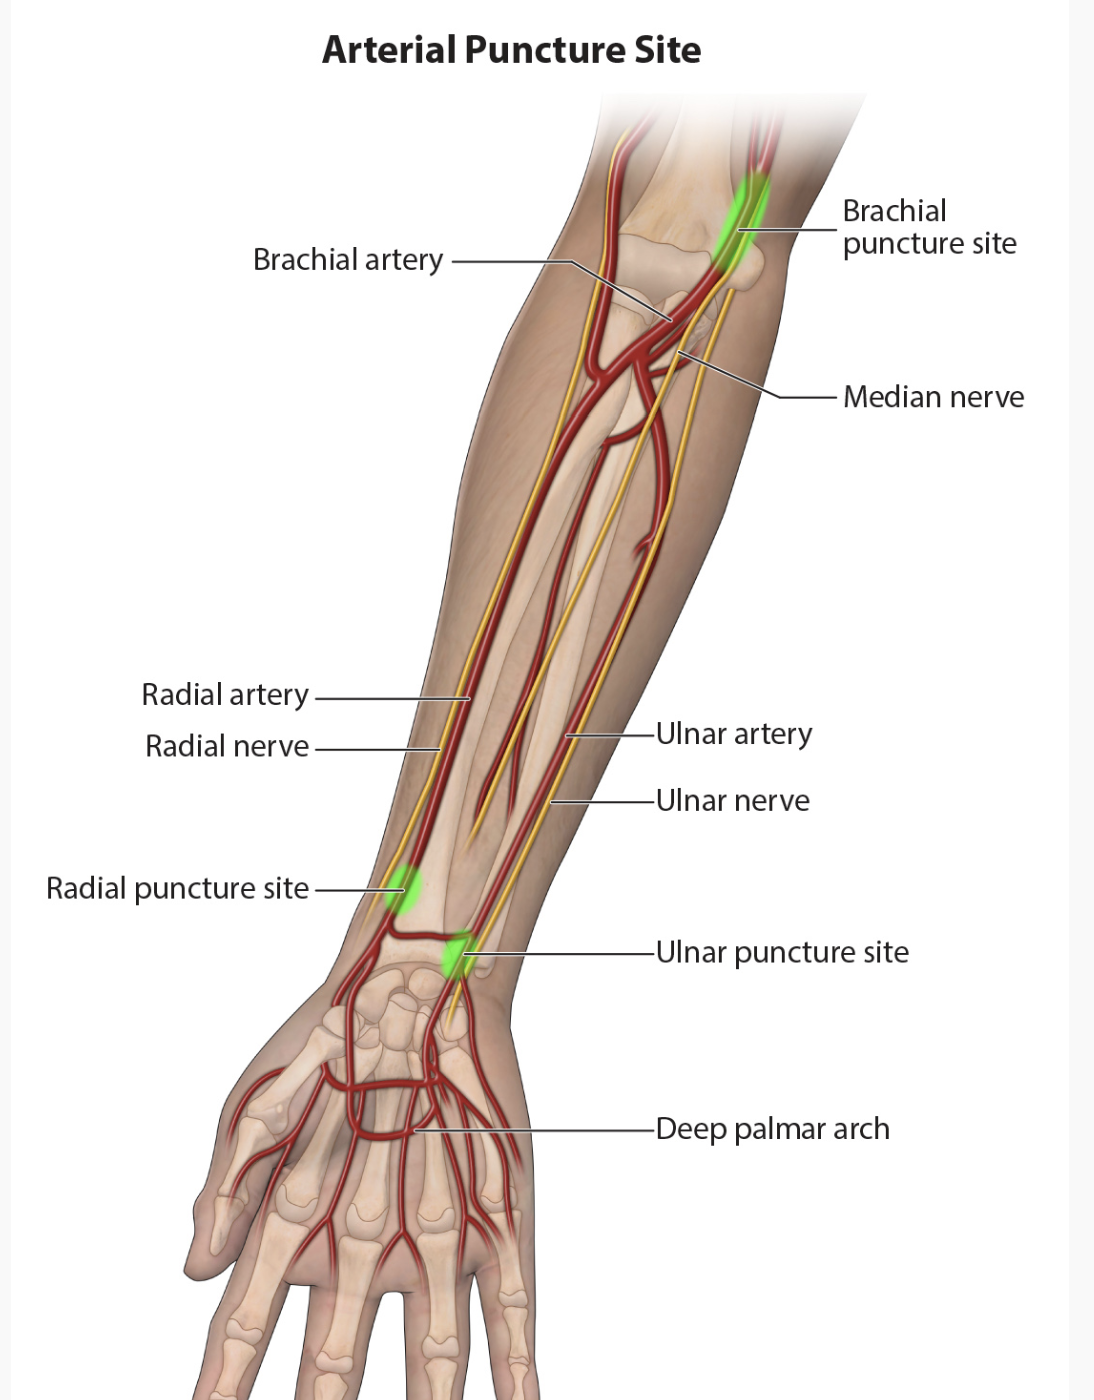

What nerve can potentially be injured by placement of a brachial arterial catheter?

Median Nerve